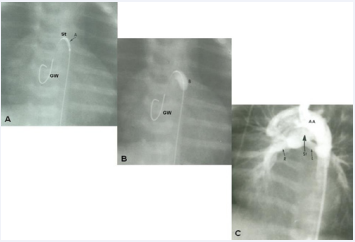

Subsequent to the stabilization of the baby, other ways of providing a more permanent blood flow to the lungs should be sought. Following the initial description of subclavian artery-toipsilateral pulmonary artery anastomosis in 1945 by Blalock and Taussig [60], a number of other types of operations/procedures have been developed to increase the pulmonary blood flow as detailed elsewhere [28,32,35]. Most cardiologists/surgeons at present prefer a modified Blalock-Taussig (BT) shunt with a Gore-Tex graft interposed between the subclavian artery and the ipsilateral pulmonary artery, described by de Leval and his associates [61]. The current thinking suggests that modified BT shunt [61], is probably most attractive procedure to adequately augment pulmonary blood flow. Some surgeons favor central, aorta to pulmonary Gore-Tex tube grafts instead. In a rare patient with principal obstruction at the level of pulmonary valve, balloon pulmonary valvuloplasty may be utilized [62,63]. A more physiologic approach of enlarging the VSD advocated by Annechino [64], is not favored by most surgeons because it is an open-heart procedure. Ductal stenting is an attractive nonsurgical alternative and is being used at some pediatric cardiology centers [65-67]. However, because of the technically demanding nature of the procedure, limited experience, and poor stent patency at follow-up [68], stenting is not currently the procedure of choice. Echocardiographic and angiographic images of some of these procedures are shown in Figures 18 to 20.

Figure 20 A) Selected cine frame demonstrating the position of a guide wire which was advanced from the aorta into the main pulmonary artery (via the ductus arteriosus) and from there into the right ventricle. The balloon/stent (St) assembly was then positioned within the ductus. The arrow demarcates the articulation (A) within the stent. B) The balloon carrying the stent is inflated within the ductus. C) An aortic arch (AA) angiographic frame shows the stented ductus (St) and good opacification of the right (R) and left (L) pulmonary arteries [66].

Figure 20: A) Selected cine frame demonstrating the position of a guide wire which was advanced from the aorta into the main pulmonary artery (via the ductus arteriosus) and from there into the right ventricle. The balloon/stent (St) assembly was then positioned within the ductus. The arrow demarcates the articulation (A) within the stent. B) The balloon carrying the stent is inflated within the ductus. C) An aortic arch (AA) angiographic frame shows the stented ductus (St) and good opacification of the right (R) and left (L) pulmonary arteries [66].